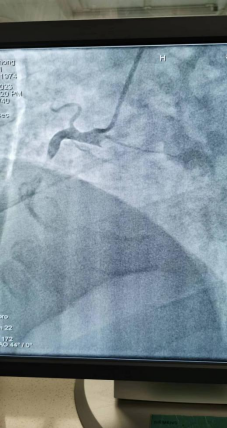

日前,商城县人民医院胸痛中心群里在半个小时内先后报告了两例来自李集乡的急性心梗患者,一场与时间赛跑,与死神博弈的生死急救快速拉开了帷幕!

急诊PCI对医院的硬件、人员配备等要求极高,能否开展急诊PCI目前已成为心血管领域彰显医院整体诊疗水平的标志。一台台成功的手术、一个个因救治及时而重获新生的患者,无不体现着我院胸痛中心日臻成熟的精确诊疗技术!也显示出我院在介入治疗领域已具备较强的综合实力。不论白昼还是黑夜、疾风或是暴雨,胸痛中心的电话就是命令!时间就是生命,时间就是心肌,胸痛中心团队始终秉持着生命至上、人民至上的理念,他们每天与时间赛跑,与死神搏斗!节省的每一分每一秒都在为急性心肌梗死患者争取生的希望,力求实现胸痛救治从急救到预防,从急病到慢病的延伸,随时待命为大别山区广大心血管疾病患者保“心”护航!